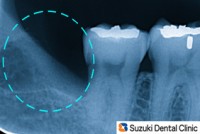

40代の男性。主訴は、「斜めに生えている親知らずのところに、物がよく詰まる。休み中に痛むと嫌なので、抜いて欲しい」でした。レントゲン撮影で歯の生え方を正しく確認したのち、短時間でスムーズに抜歯ができました。

左:術前